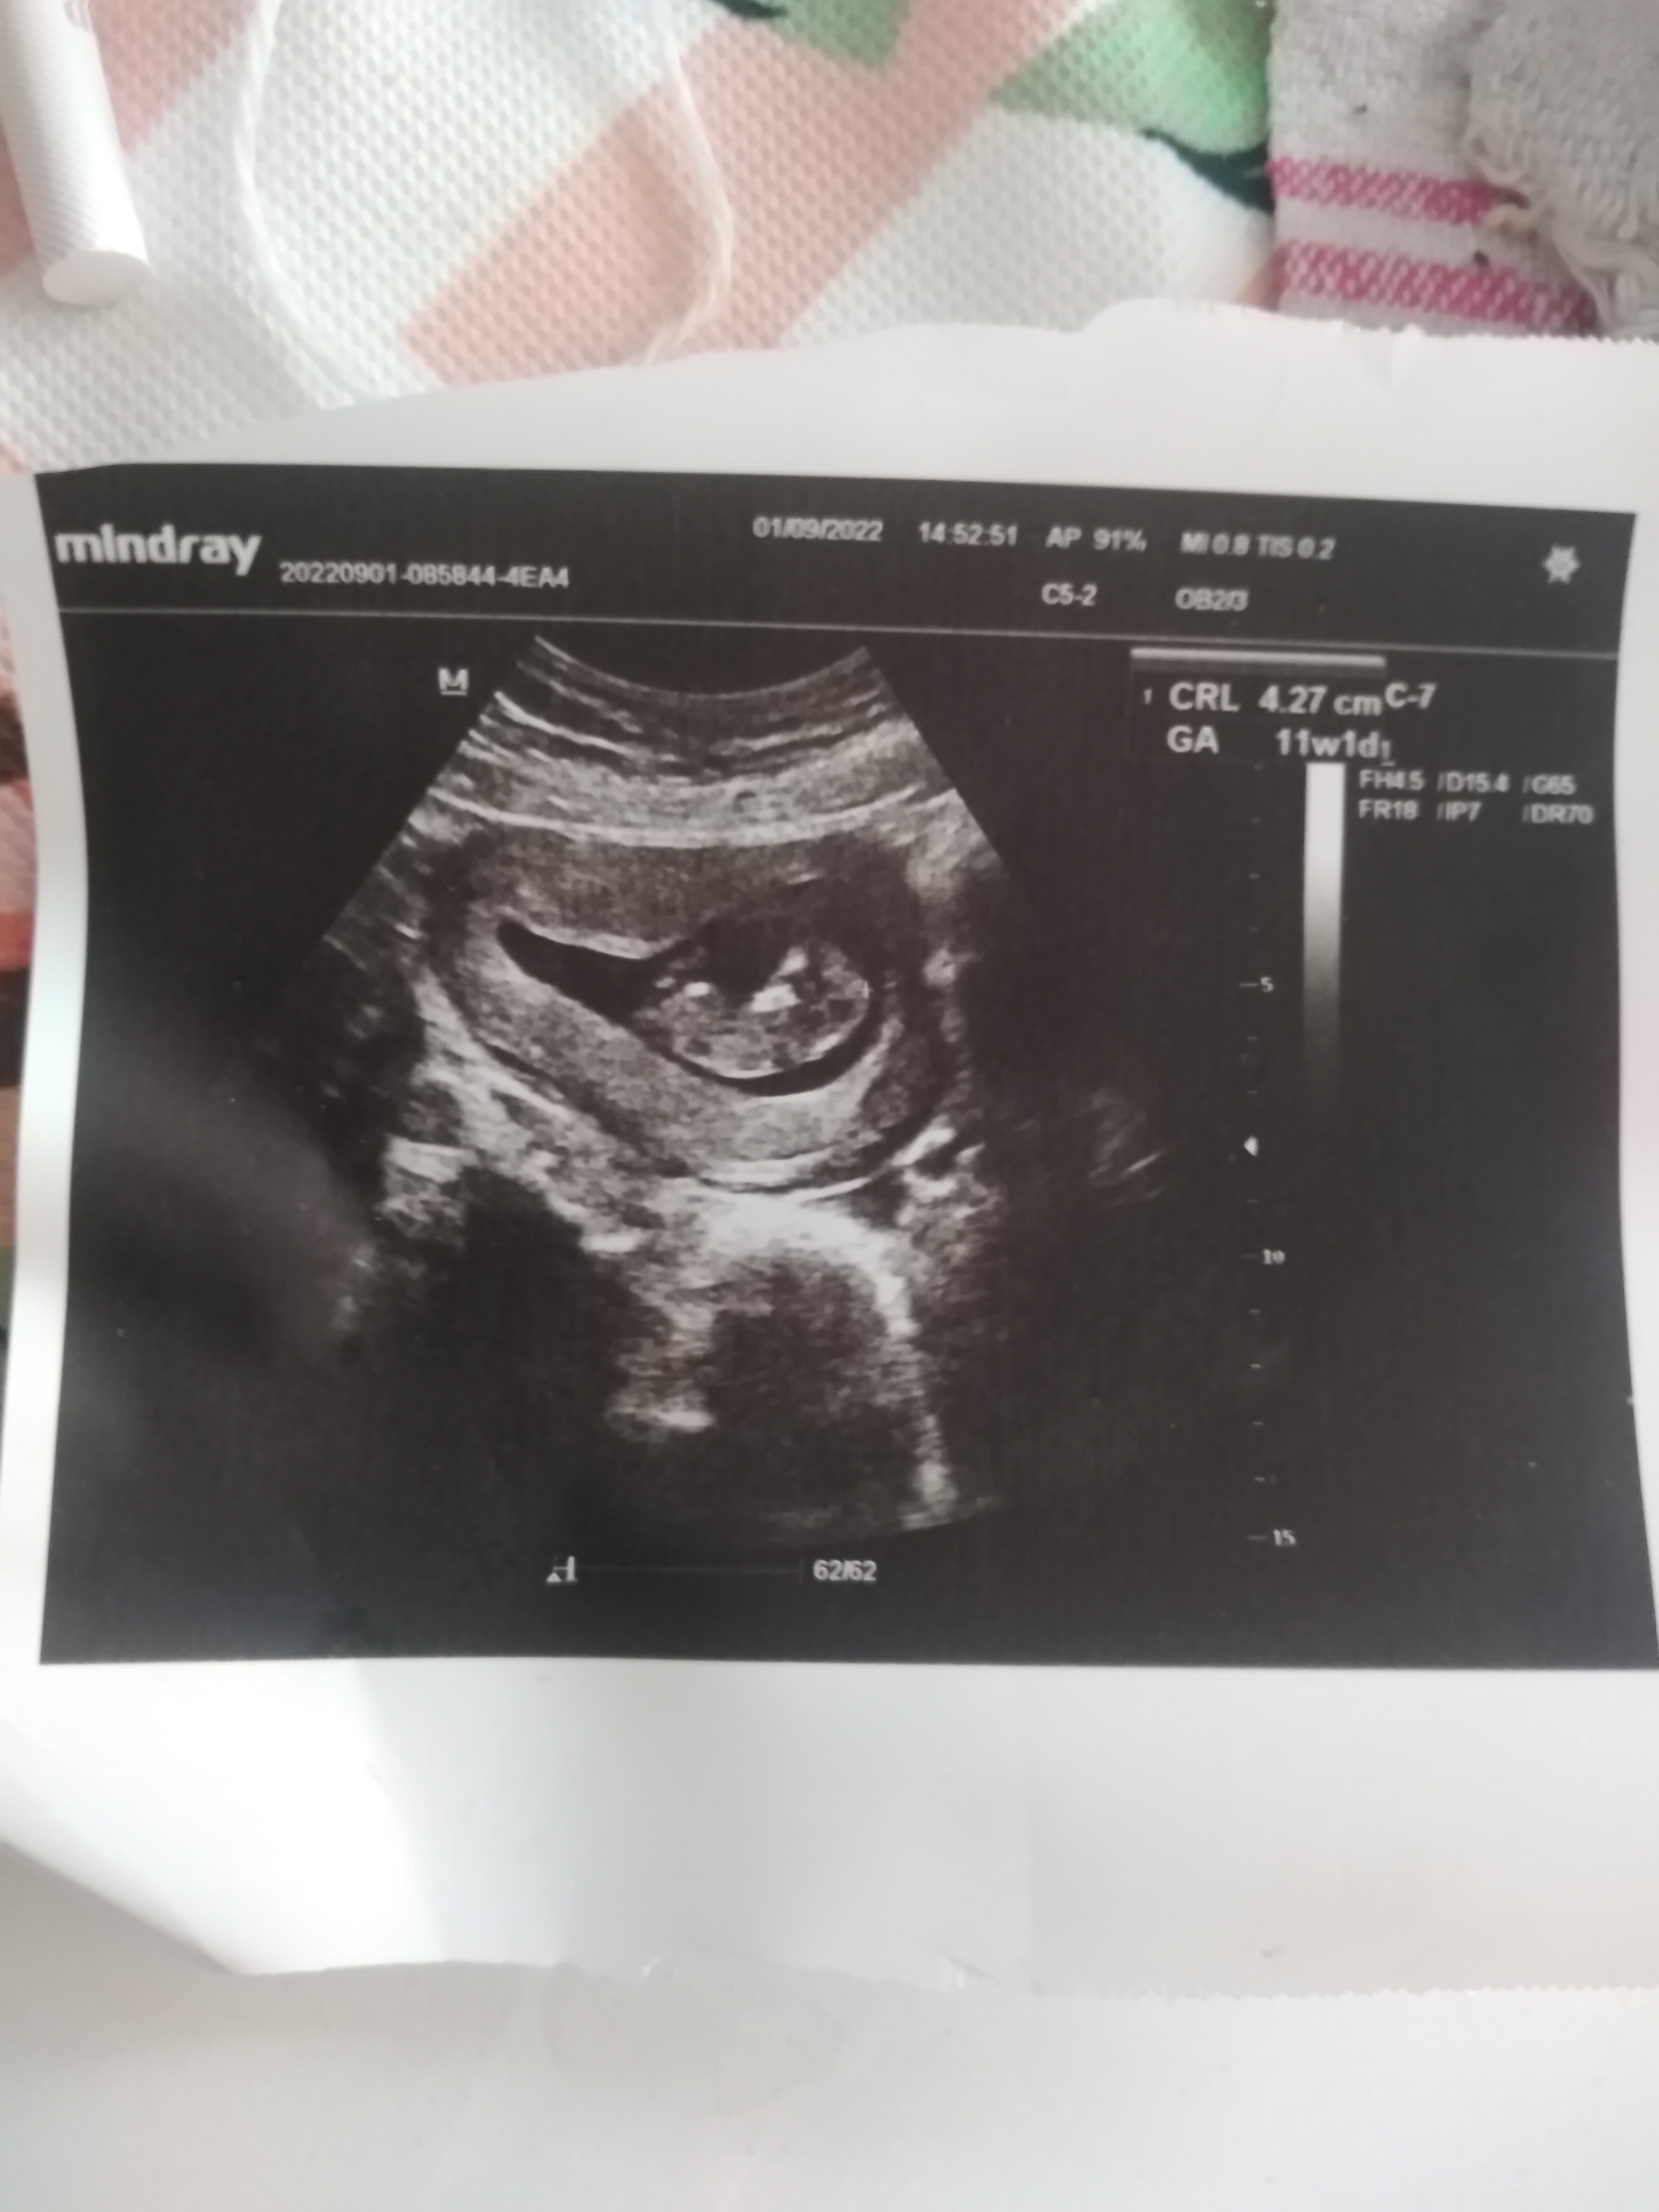

Bebeğimin cinsiyetini ogrenebilirmiyim? 11hafta 1 gunluk

Selamlar bir tanem, bizimkisi ilgili teoriye göre tahmindir bilginiz olsun. Görüntü sola biraz daha yakın olduğu için erkek diyebiliriz. Ama doğrusunu Allah bilir. Sevgiler sunuyorum.

Bu arada Nub teorisine göre baktım resmi siz atınca bunda da kız görünüyor 🙂 Elinizde başka foto var ise ekleyebilir misiniz ?